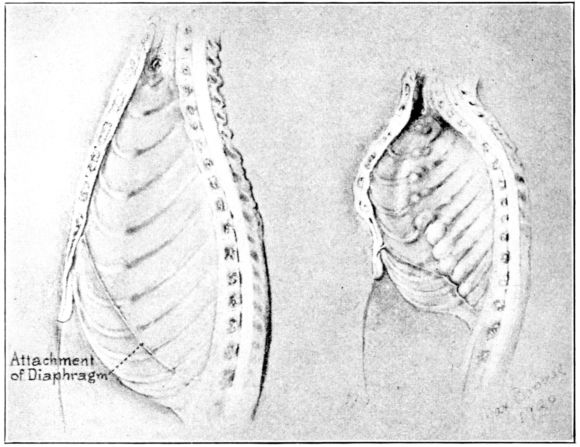

| 142. | Chest walls of normal and rachitic rats of the same age | 383 |

| 143. | Interior of specimens in Fig. 142 | 384 |